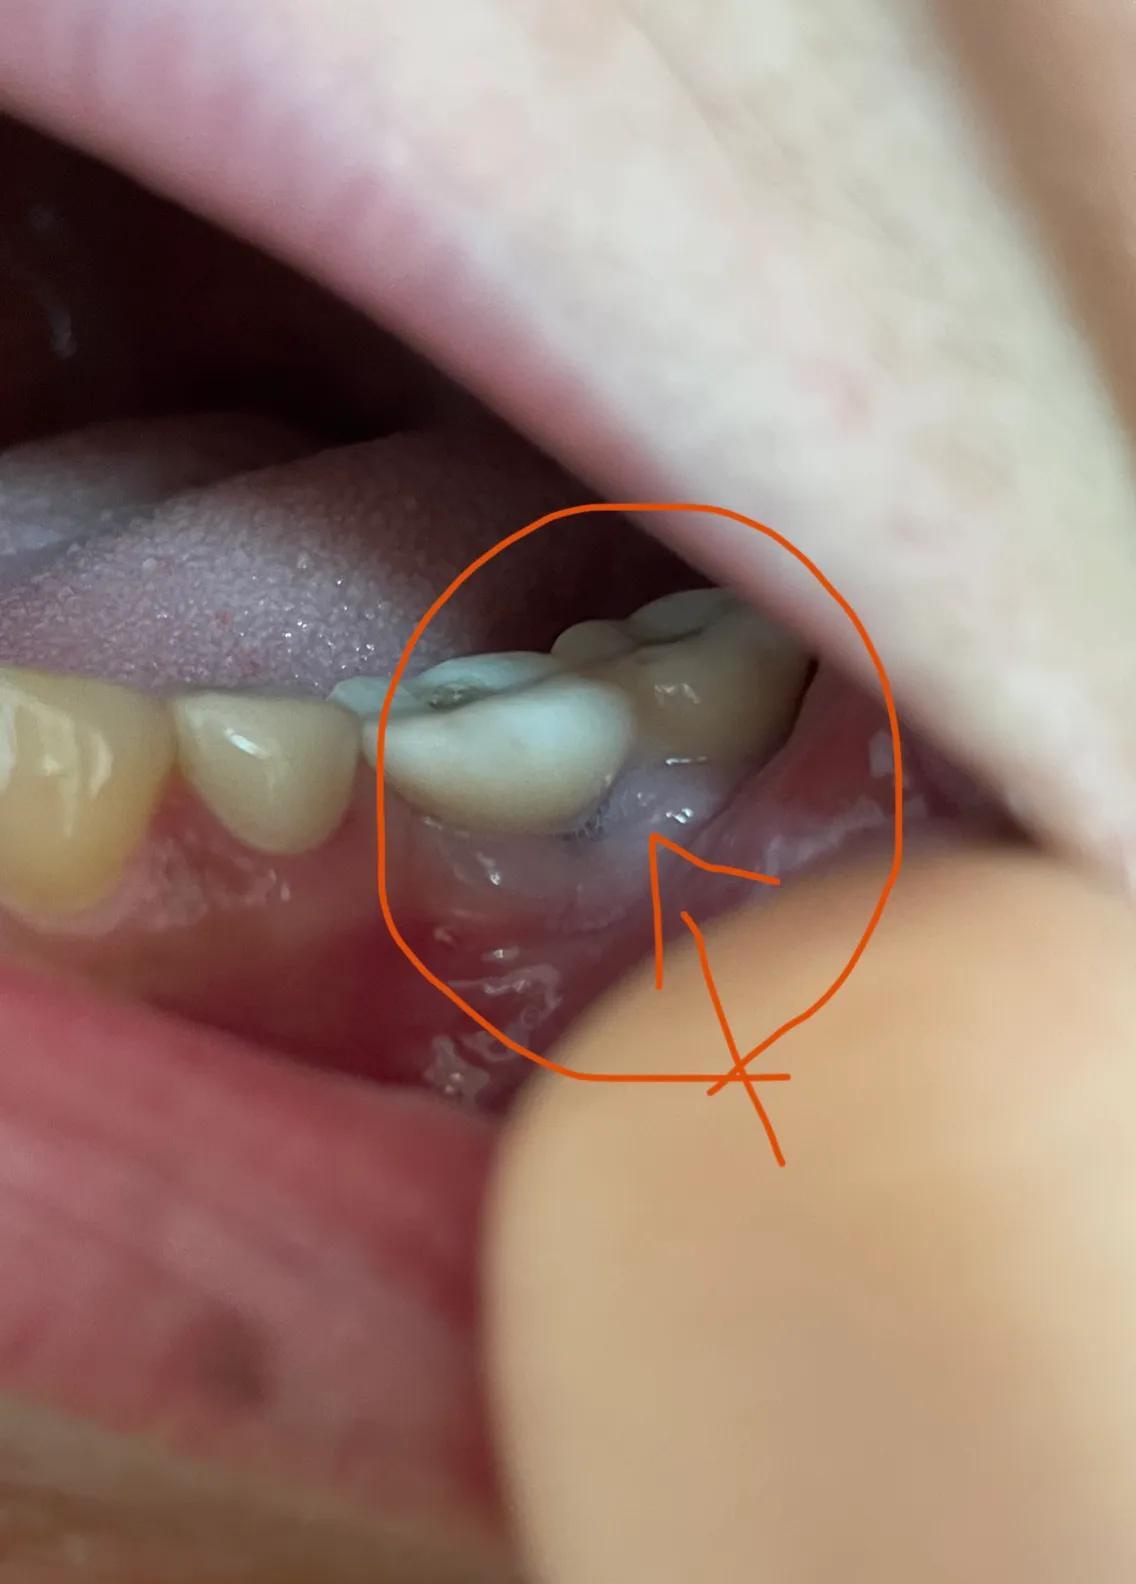

第二副牙帶好 發(fā)現(xiàn)牙齦又缺肉了 更別提貼合牙齒了 而且是一直的疼 一直難受

牙齦是外翻和牙齒分開(kāi)的 顏色發(fā)白 和其他部位牙齦不是一樣顏色

我不是專業(yè)醫(yī)生 不懂他們所說(shuō)的正常現(xiàn)象都包括什么 要怎么后期維護(hù) 我現(xiàn)在先不講看不見(jiàn)的難受 疼 先講直觀能看見(jiàn)的 他們哪位醫(yī)生可以做到把大米粒塞到牙齒下面 和將近半厘米的塑料條塞過(guò)他們的牙齒 吃過(guò)東西就要用沖牙器 不然隔頓就臭了

沒(méi)辦法自己又出去拍片子 找原因 看了幾家醫(yī)院 才知道連種植體也種偏了 牙冠也沒(méi)有就位………